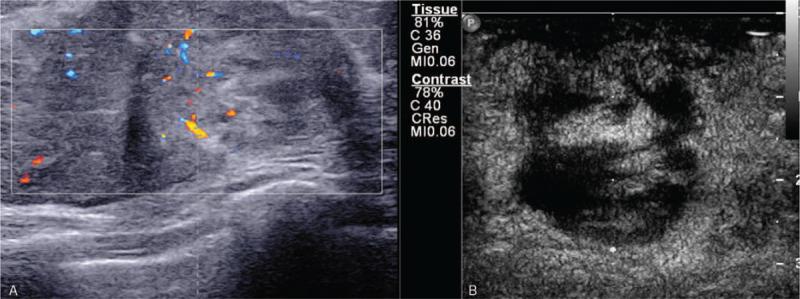

The tumor mimicked idiopathic granulomatous mastitis on magnetic resonance imaging (MRI) at the first presentation. Contrast-enhanced ultrasound (CEUS) was performed for further lesion characterization and showed heterogeneous rapid hyper enhanced. An ultrasound-guided core needle biopsy was performed, and the pathology report indicated a breast angiosarcoma.

After 8 months later, the tumor recurred, CEUS and MRI examination suggested PBA recurrence, then re-excision with implant removal was performed, the patient had a lung metastasis 4 months later eventually died 22 months after diagnosis.

It is not easy to diagnose PBA with the radiographic examination. This case's importance is by combining CEUS and MRI to reflect enhanced morphology and hemodynamic characteristics of PBA and help diagnose breast angiosarcomas.

肿瘤在初次就诊时的磁共振成像(MRI)上模拟特发性肉芽肿性乳腺炎。为进一步明确病变特征,进行了对比增强超声(CEUS)检查,显示不均匀快速高增强。进行了超声引导下的核心针活检,病理报告提示乳腺血管肉瘤。

8 个月后,肿瘤复发,CEUS 和 MRI 检查提示 PBA 复发,随后进行了再次切除和植入物取出,4 个月后患者出现肺转移,最终在诊断后 22 个月死亡。

影像学检查诊断 PBA 并不容易。这个病例的重要性在于结合 CEUS 和 MRI 反映 PBA 的增强形态和血流动力学特征,有助于诊断乳腺血管肉瘤。